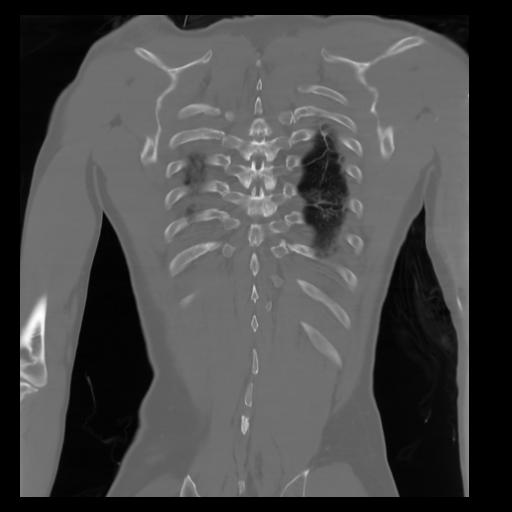

29 CUERPO,CE,Coronal,3.000,CUERPO,Coronal,